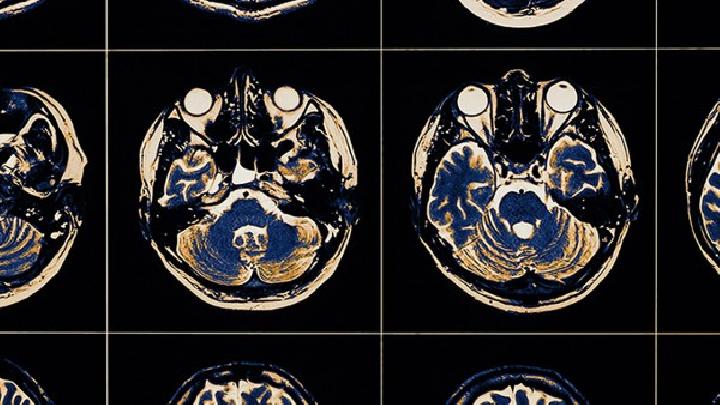

病理性脑萎缩是一种由多种原因引起脑组织体积由大到小的阑珊性疾病,主要由血管疾病(如脑动脉硬化、脑梗死、脑出血、高血压、冠心病等)、退行性疾病(如高发病率硬化等)、内排泄疾病(如慢性糖尿病、甲状腺机能亢进、维生素缺乏等)、中毒(如金属中毒、气体中毒、酒精中毒等)、感染(如脑炎等)、脑损伤引起的脑本色破碎和神经器官细胞萎缩、变形、消散。

脑血管疾病是脑萎缩最常见的原因。主要有脑梗死、脑血栓形成、脑出血等疾病,由于血液粘度增加、血流缓慢、血管壁粗糙等一系列因素,导致壁血栓形成、血管腔狭窄甚至堵塞,导致脑组织细胞缺血、缺氧、萎缩甚至坏死,最终形成脑萎缩、痴呆甚至死亡。